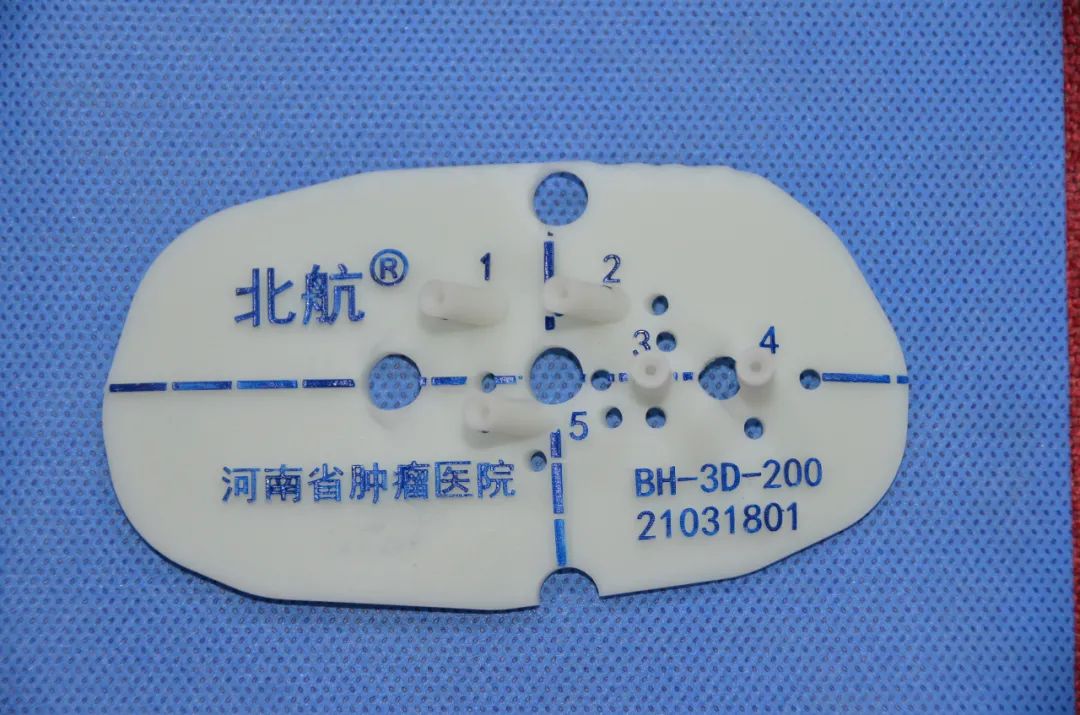

甲状腺是人体中非常重要的内分泌器官,外形像一只美丽的蝴蝶,通过分泌甲状腺激素促进物质和能量的代谢,对人体的多系统具有重要影响。近年来,随着人们体检意识的增强和超声诊疗技术的迅猛发展,甲状腺恶性结节的检出率呈逐年增高的趋势,而一旦确诊,颈部这只美丽的蝴蝶就面临着折翼的风险——外科手术切除。腺体切除、颈前瘢痕、终身服药像一幕幕阴霾,笼罩在患者的头上。 患者小Y是一个23岁年轻美丽的女孩儿,在哈医大一院超声医学科进行超声检查后,发现右侧叶有一枚大小约0.8cmx0.6cmx0.8cm的TI-RADS 4c类结节(图1),并且经过穿刺病理证实为甲状腺乳头状癌。这如同一个晴天霹雳般的坏消息,让这个女孩儿痛苦不已。如果选择手术切除,术后颈部的瘢痕、终身服药的不便、尚未结婚怀孕的现实难题,让小Y难以接受传统手术疗法。在了解到她的困扰后,哈医大一院超声医学科介入团队迅速启动科内会诊及病例讨论机制,在学科主任吴长君教授的提议下,决定采用超声引导下的射频消融治疗,对小Y的恶性结节进行局部灭活,并且尽可能保留正常腺体。通过术前审慎评估,细致准备,消融手术由超声医学科王俊峰副教授主刀。在实时超声的引导下,射频消融针精准的进入恶性病灶内,仅用时3分钟左右,消融范围就完全覆盖病灶(图2)。 治疗过程中,超声介入团队配合默契,采用多种技术保障患者安全,避免了甲状腺周围重要组织(血管、神经)的损伤。治疗取得了圆满成功。术后,小Y开心的笑了,超声介入团队也由衷的为她感到高兴(图3)。 哈医大一院超声医学科主任、博士生导师吴长君教授介绍,超声引导下射频消融治疗甲状腺乳头状癌,具有非常多的优点。在保障治疗效果的同时,可以满足患者个性化的需求。射频消融用时短,术后恢复快,无需终身服药,并且避免了颈部瘢痕,尤其对于爱美女性及拒绝终身服药的患者非常友好,是一种值得大力推广和应用的治疗技术。哈医大一院超声医学科介入团队秉承不断进取、精益求精的理念,着力打造甲状腺疾病诊疗一体化平台,为守护龙江人民的健康不懈努力!